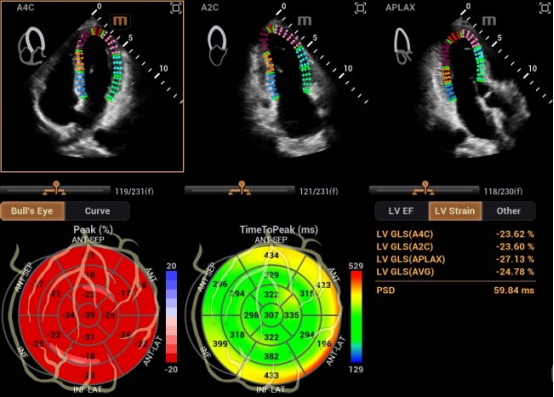

在研发中,迈瑞研发团队另辟蹊径,推出了自动左心室应变评估 Auto Strain LV 。该功能不再依赖心电信号作为“时间坐标”,而是让AI直接识别心脏机械运动的关键节点——当二尖瓣关闭、主动脉瓣开放,这些瓣膜运动的瞬间,就是心脏收缩与舒张的自然锚点。

迈瑞也在与尹立雪教授团队牵头的合作项目中,挖掘出自动左心室应变评估 Auto Strain LV 更多的临床应用价值,成功让心肌应变检测技术摆脱“心电图(ECG)”的束缚。尹教授表示:“基于人工智能的图像技术,现在已实现无需同步心电图的自动心肌应变分析。该技术操作便捷,检测结果与传统方法高度一致,且能早于传统指标识别心肌功能异常,为疾病早期干预提供关键支撑。”